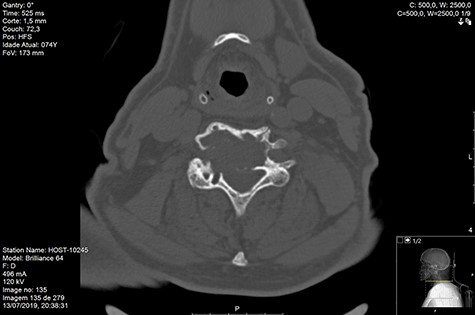

Computed tomography (CT) (Figs 1–3) and magnetic resonance imaging (MRI) (Figs 4–6) of the cervical spine were performed and revealed a lytic lesion involving most of C4, C5 and C6 vertebral bodies with bilateral extension to the posterior spinal elements of C4 and C5 and complete disruption of C4-C5 and C5-C6 intervertebral discs.

The Spinal Instability Neoplastic Score (SINS) [4, 6, 7] for assessing spinal instability from metastatic disease was used and the lesion was deemed unstable (SINS 13), with impending risk of increased neurological damage.